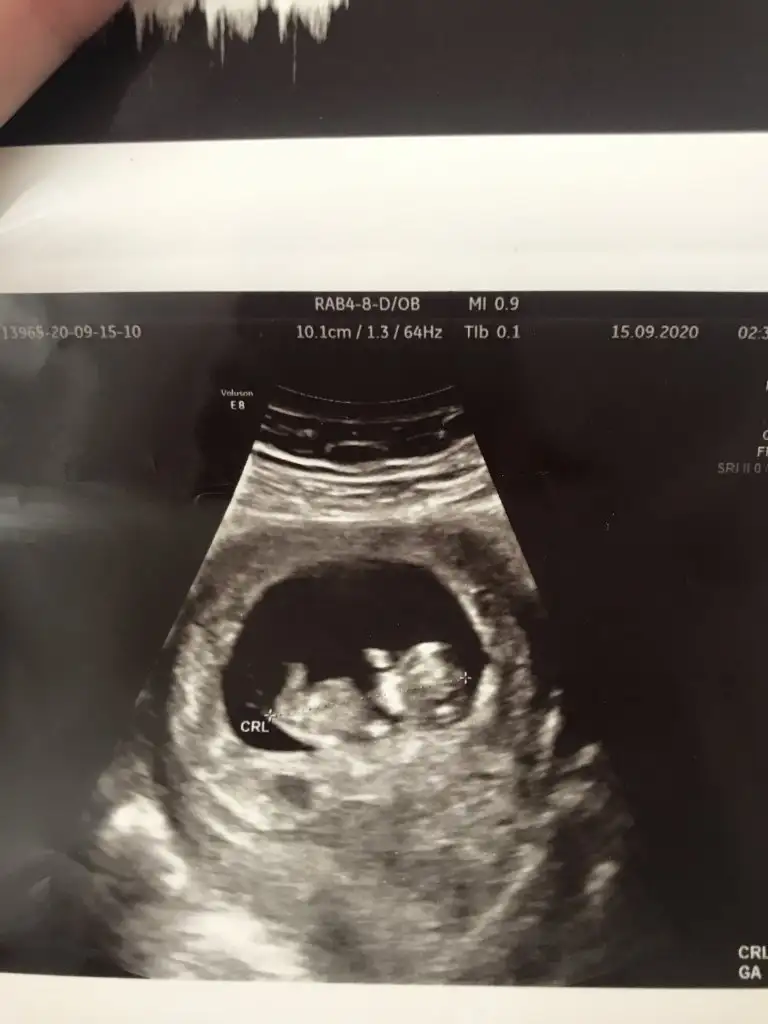

KızKızlar sizce benimkinin cinsiyeti nedir 2 3 hafta geçse de kesin bir şekilde öğrensek

Erkek paralel parlak bacaklar yok kızda oluyor diye bilyorumKızlar sizce benimkinin cinsiyeti nedir 2 3 hafta geçse de kesin bir şekilde öğrensek

Bana da erkek gibi geldiKızlar sizce benimkinin cinsiyeti nedir 2 3 hafta geçse de kesin bir şekilde öğrensek

Bence kiz❤Arkası hafif dönük, cinsiyet tahminlerini alayım

Senin bebisi erkek diye dusunuyorum❤Kızlar sizce benimkinin cinsiyeti nedir 2 3 hafta geçse de kesin bir şekilde öğrensek

Kuzum gittiğimde günüm 10+2 ydi yani bu ultrason resminde crl de 3.38 canım kalp atışı da 180 benim ki baya heyecanlı